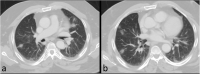

Purpose: Coronavirus disease 2019 (COVID-19) is caused by a novel strain of coronavirus named severe acute respiratory syndrome coronavirus 2 (SARS-CoV-2) that has quickly spread around the globe. Health care facilities in the USA currently do not have an adequate supply of COVID-19 tests to meet the growing demand. Imaging findings for COVID-19 are non-specific but include pulmonary parenchymal ground-glass opacities in a predominantly basal and peripheral distribution.

Results: Each patient had suspicious imaging findings for COVID-19, prompting the interpreting radiologist to suggest testing for COVID-19. All 3 patients turned out to be infected with COVID-19, and one patient is the first reported case of the coincident presentation of COVID-19 and an intraparenchymal hemorrhage.

Conclusion: Using imaging characteristics of COVID-19 on abdominal or neck CT when a portion of the lungs is included, patients not initially suspected of COVID-19 infection can be quarantined earlier to limit exposure to others.